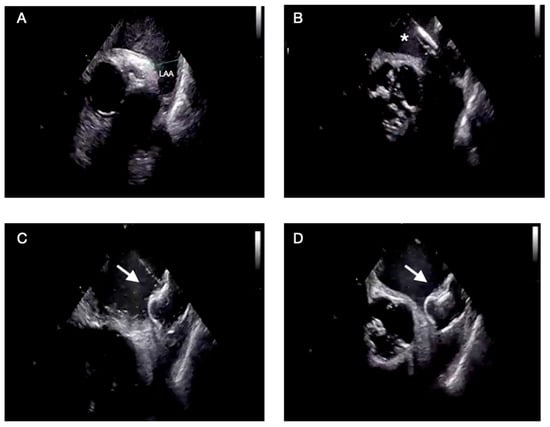

Intracardiac Echocardiography in Structural Heart Interventions: A Comprehensive Overview

by Francesco Leuzzi, Ciro Formisano, Enrico Cerrato, Antongiulio Maione, Tiziana Attisano, Francesco Meucci, Michele Ciccarelli, Carmine Vecchione, Gennaro Galasso and Francesca Maria Di Muro

Intracardiac echocardiography (ICE) is increasingly recognized as a valuable imaging modality in structural heart interventions, offering high-resolution, real-time visualization from within the cardiac chambers. Originally developed for electrophysiologic procedures, ICE has expanded its use across a broad spectrum of structural interventions, including atrial [...] Read more.

Intracardiac echocardiography (ICE) is increasingly recognized as a valuable imaging modality in structural heart interventions, offering high-resolution, real-time visualization from within the cardiac chambers. Originally developed for electrophysiologic procedures, ICE has expanded its use across a broad spectrum of structural interventions, including atrial septal defect (ASD) and patent foramen ovale (PFO) closure, left atrial appendage occlusion (LAAO), transseptal puncture guidance, transcatheter edge-to-edge repair (TEER), balloon mitral valvuloplasty, and both mitral and tricuspid valve therapies. This review outlines the current role and technical principles of ICE, with an emphasis on catheter design, image acquisition protocols, and the emerging potential of 3D ICE. Comparisons with transesophageal echocardiography (TEE) and fluoroscopy are discussed, highlighting ICE’s ability to support minimally invasive, sedation-sparing procedures while maintaining procedural precision. We provide a focused analysis of ICE-guided applications in specific clinical scenarios, emphasizing its role in anatomical assessment, device navigation, and intra-procedural monitoring. Data from recent clinical studies and registries are reviewed to assess safety, feasibility, and outcomes. Practical considerations including operator learning curve, workflow integration, and limitations such as cost and field of view are also addressed. Lastly, we explore future directions including advanced 3D imaging, fusion imaging, artificial intelligence integration, and robotic catheter systems. Full article